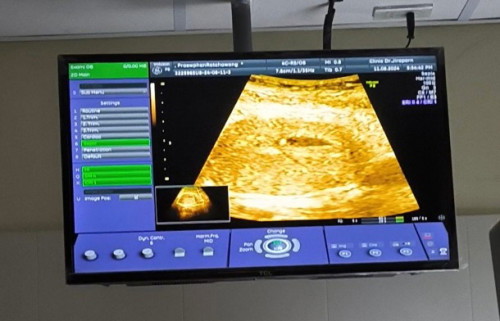

วันนี้ไปซาว์มาครับหมอบอกเจอแต่ถุงไข่แดง อาจจะยังครรภ์อ่อนอยู่ ตอนนี้หมอบอกประมาณ5สัปดาห์ อีก2อาทิตย์ให้ไปซาว์ใหม่

ปกติค่ะ ท้องอ่อนมาก อีก2อาทิตย์ขอให้โชคดีนะคะ